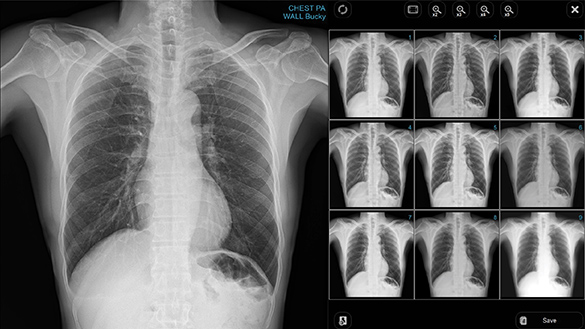

RadTrainer supports real clinical preparation by guiding patient positioning and exposure setup. It uses an extensive high-resolution image library covering 23 body parts and 337 positioning scenarios, based on real images used in general hospitals for realistic training and image review.

Perform X-ray exposure within the simulation environment and immediately review the acquired images.

9 Image Presets

Nine image presets are generated from a single exposure, allowing users to select the most appropriate image without retaking X-rays.